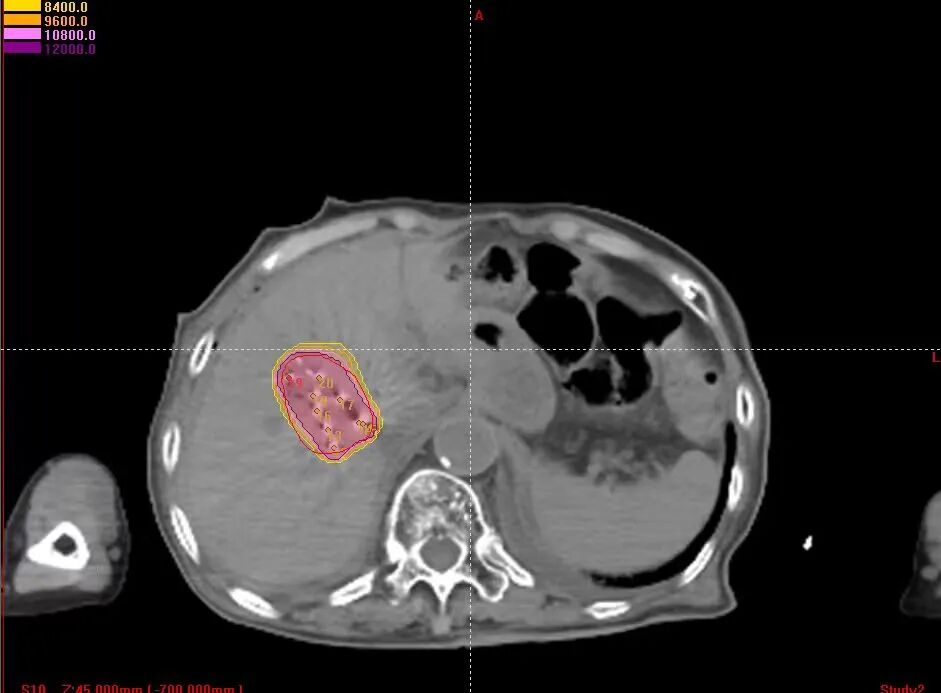

3、术后精准验证:术后通过CT扫描重建粒子分布影像,显示碘125粒子均匀分布覆盖病灶,无冷区,与术前规划方案进行剂量对比验证,确保碘125粒子分布完全符合预设要求。

1、术前精准规划:制定三维治疗计划系统(TPS)勾画肿瘤靶区,精确规划粒子的分布范围、数量、活度及间距,确保粒子均匀覆盖整个病灶,同时避开周围的血管、胆管等正常组织,实现“局部剂量高、周围正常组织损伤小”的治疗目标。